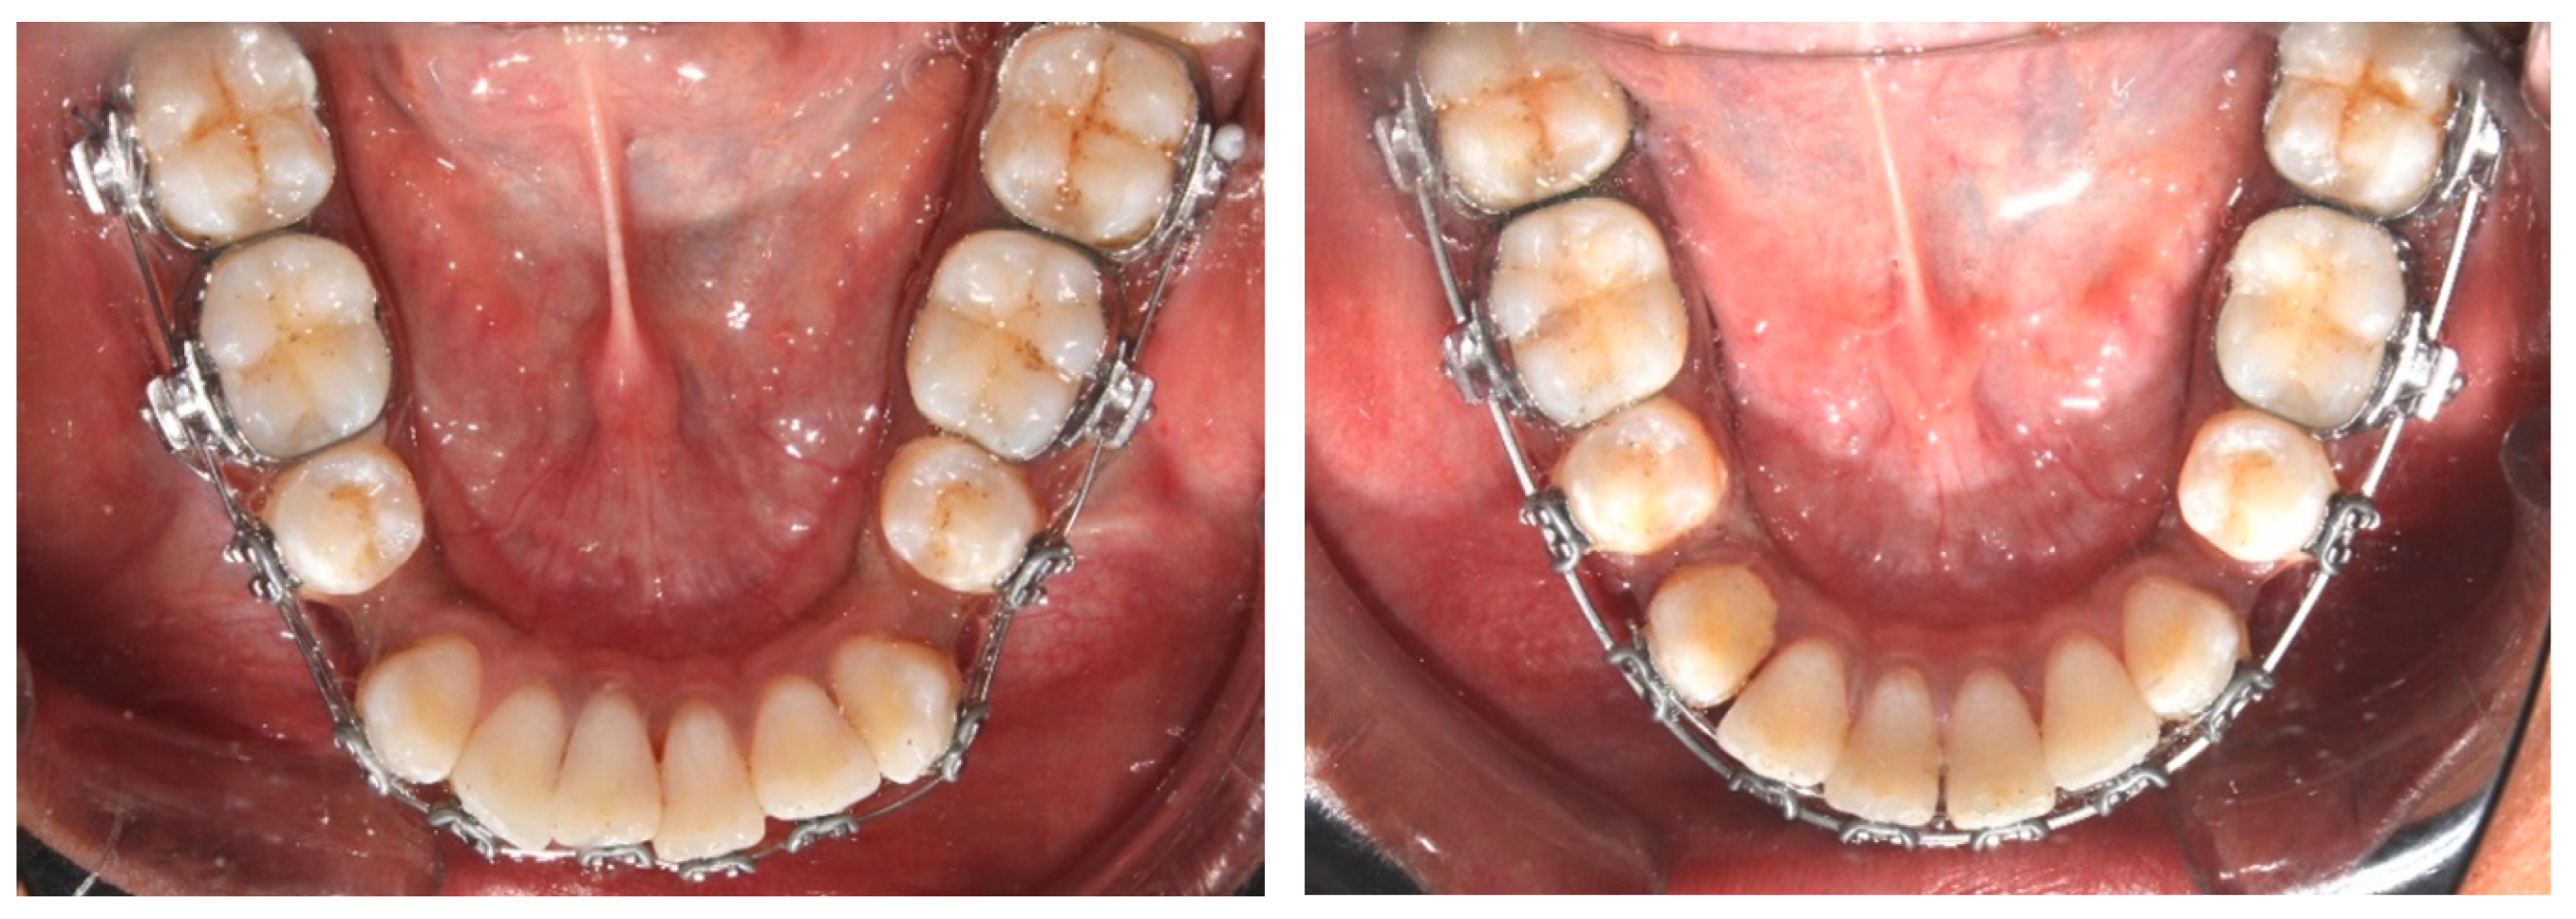

2.4. Orthodontic Procedure

- T0—at the initiation of orthodontic treatment.

- Tx—at the termination of the decrowding stage when LII was less than 1 mm.